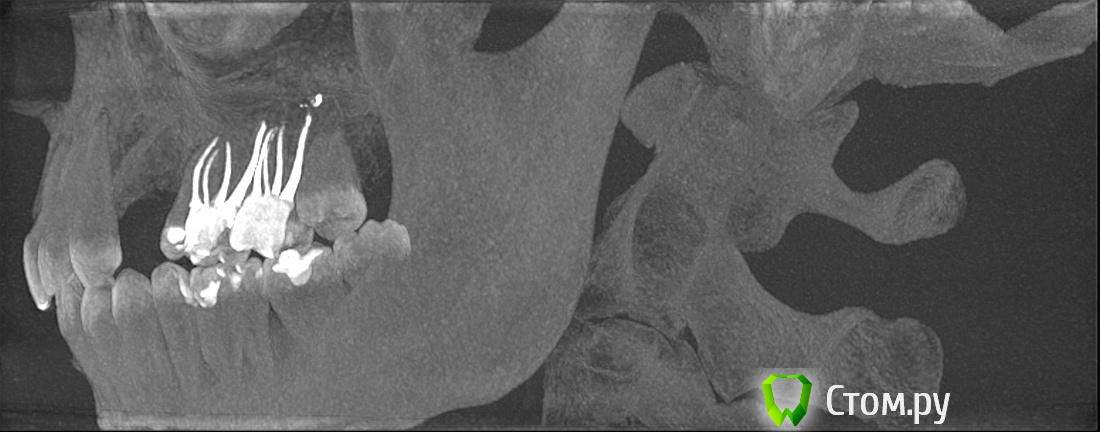

winnt Опубликовано 18 июля, 2014 Автор Поделиться Опубликовано 18 июля, 2014 Еще добавлю срез КТ, между 7 и 8 : Ссылка на комментарий

winnt Опубликовано 18 июля, 2014 Автор Поделиться Опубликовано 18 июля, 2014 То есть 7ой зуб чувствует холод? Болит меньше когда прикладываете? А скололся скорее всего из-за кариеса, антогонист скол не вызовет, либо стираемость может быть и увеличение чувствительности. Пломбу вам случаем не завысили?Холод чувствует, но как-то тупее чем здоровый зуб и боль остается дольше после холодного;Когда прикладываю болит больше и после того как убираю боль "остается" дольше чем в здоровом;Скололся от удара нижней челюстью об торпеду авто;Пломбу не завысили, это точно. Покрутил в КТ этот зуб и стало чуть страшно будто от корня этого зуба "что-то растет" прямо в НЧ.канал: Ссылка на комментарий